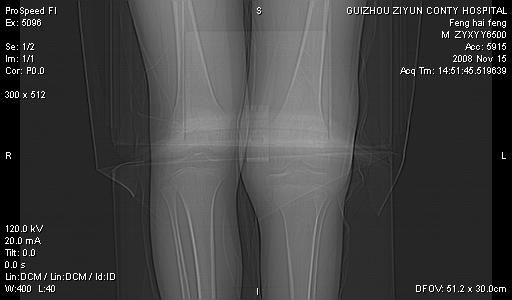

标题: CT16656:M 14Y 左膝关节肿胀一年余。其余病史不详。 [打印本页]

标题: CT16656:M 14Y 左膝关节肿胀一年余。其余病史不详。

好大的左腿!考虑左侧髌骨结核,左膝关节滑膜肿胀、增厚,关节囊积液。